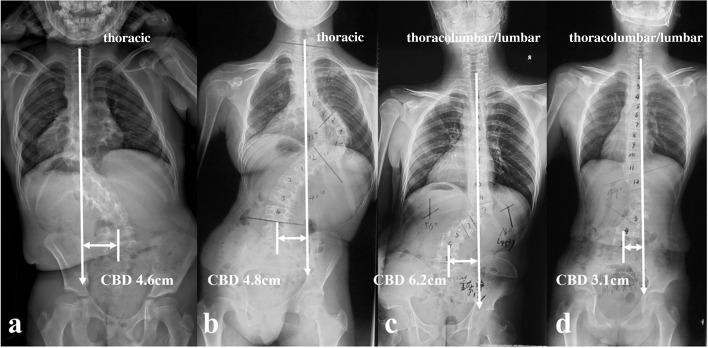

All the recruited patients were stratified according to the location of dystrophic curve apex: thoracic group, 4 cases (26.7%) (Fig. 1a, b); thoracolumbar/lumbar group, 11 cases (73.3%) (Fig. 1c, d). Among them, 1 patient in thoracic group and 3 patients in thoracolumbar/lumbar group received staged surgery with combined posterior-anterior or anterior- posterior approach (Table 1), while the rest 11 patients (73.3%) underwent posterior-only spinal instrumentation and fusion. Supplementary anterior fusion utilizing structural fibular allograft (2 patients) (Figs. 2, 8) or autogenous rib grafts (1 patient) (Fig. 3) was applied when the pedicle screw density in the apical region was distinctively low due to pedicle dystrophy disabling screw insertion. Stage 1 anterior release involving intervertebral disc resection and autogenous rib grafting was performed in 1 patient of thoracolumbar/lumbar group, followed by skull-femoral traction for 2 weeks and subsequent stage 2 posterior spinal correction and fusion.